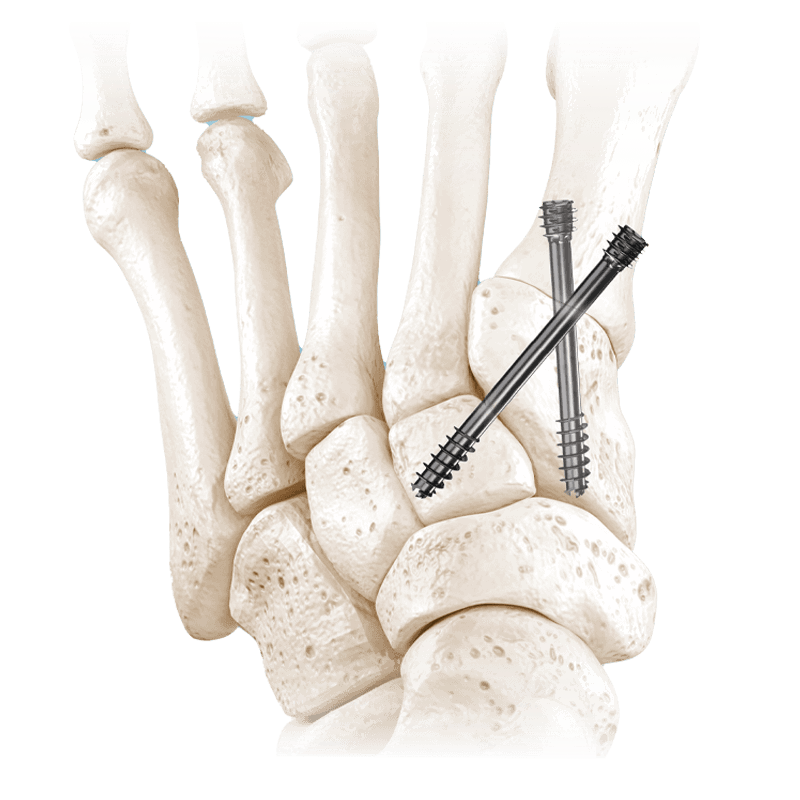

Fixation Devices - Compression Hardware

IBS™-B Beveled Screw System

IBS™-B Beveled Screw System delivers the strength, control, and versatility your MIS workflow demands.